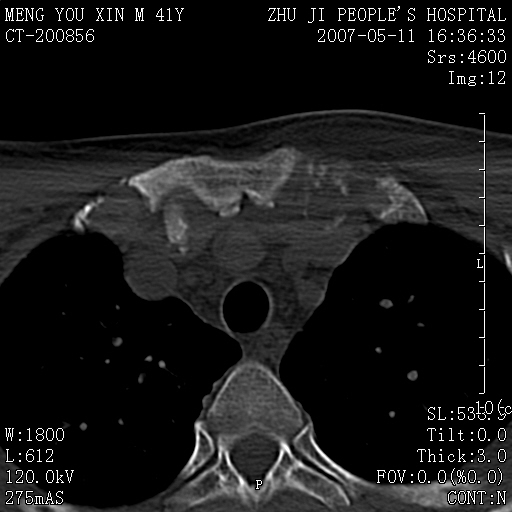

标题: CT8190:左锁骨胸骨端骨病,请会诊.

一周前左肩部酸痛,三天前颈部扭伤,后颈部摄片示颈椎病.现胸锁关节处肿痛明显.无发热.自诉三年前车祸安全气囊弹出.

左侧锁骨近端膨大,骨皮质中断,并见少许骨膜反应,内见破坏,边缘见筛孔征,无硬化.因此考虑骨巨细胞瘤可能.

1,不支持结核,此例胸壁肿胀不明显,锁骨后方是局限性肿物而非脓肿,考虑为恶性肿瘤2,左侧锁骨近端膨大,骨皮质中断,并见少许骨膜反应,内见破坏,边缘见筛孔征,无硬化.因此考虑骨巨细胞瘤可能.